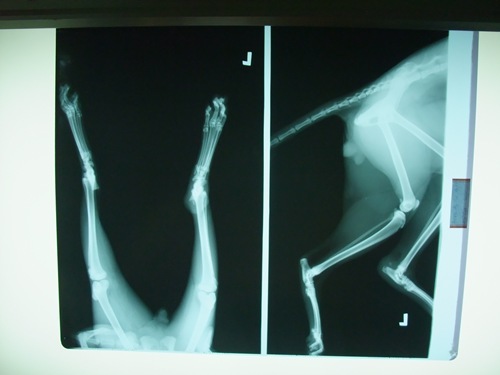

主題: 雲林虎斑傷貓 申請者姓名: Vivi Sung 花色: 申請日期: 2012-07-03 14:42:57 申請者部落格: 申請者臉書網址: 所在縣市/合作醫院: 台南市/奇異果動物醫院 治療費用: 8700元 需求人數: 10人 已結案 (2012-12-08 18:40:35) 報名人員: Michelle、Michelle(已付款)、Wen Tzu Yang(已付款)、Emily Chou(已付款)、Emily Chou(已付款)、波波(已付款)、劉明玲、Han Han Wang(已付款)、konana(已付款)、amelie(已付款)、lunyi(已付款)、lunyi、Welltea Wu(已付款)、 候補人員: 小舟、小舟、 動物病情說明: 5/30網友樊迎慶求援傷貓,於5/31轉診至台南奇異果動物醫院..外傷+骨折.且阿基里斯腱斷裂也感染的狀況下.先予以穩定才可以治療

5/31血液檢查(紅白血球+生化檢驗)$880

3合一檢驗 $600麻醉清創$1500X光$320皮下點滴$200驅蟲$100除蚤$150